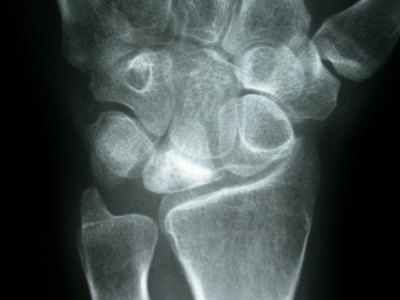

Fortgeschrittenes Stadium mit bereits

eingetretener Höhenminderung im Mondbein

Stadium III a: Per Röntgenaufnahme lässt sich der Zerfall des Knochens in mehrere Teile erkennen. Das Kernspintogramm gibt Aufschluss darüber, ob der Knochen noch vital ist.

Stadium III b: Die Fragmente des Knochens sinken in sich zusammen („karpaler Kollaps“).

Stadium IV: Im Röntgenbild zeigt sich eine Deformität auch der übrigen Handwurzelknochen.